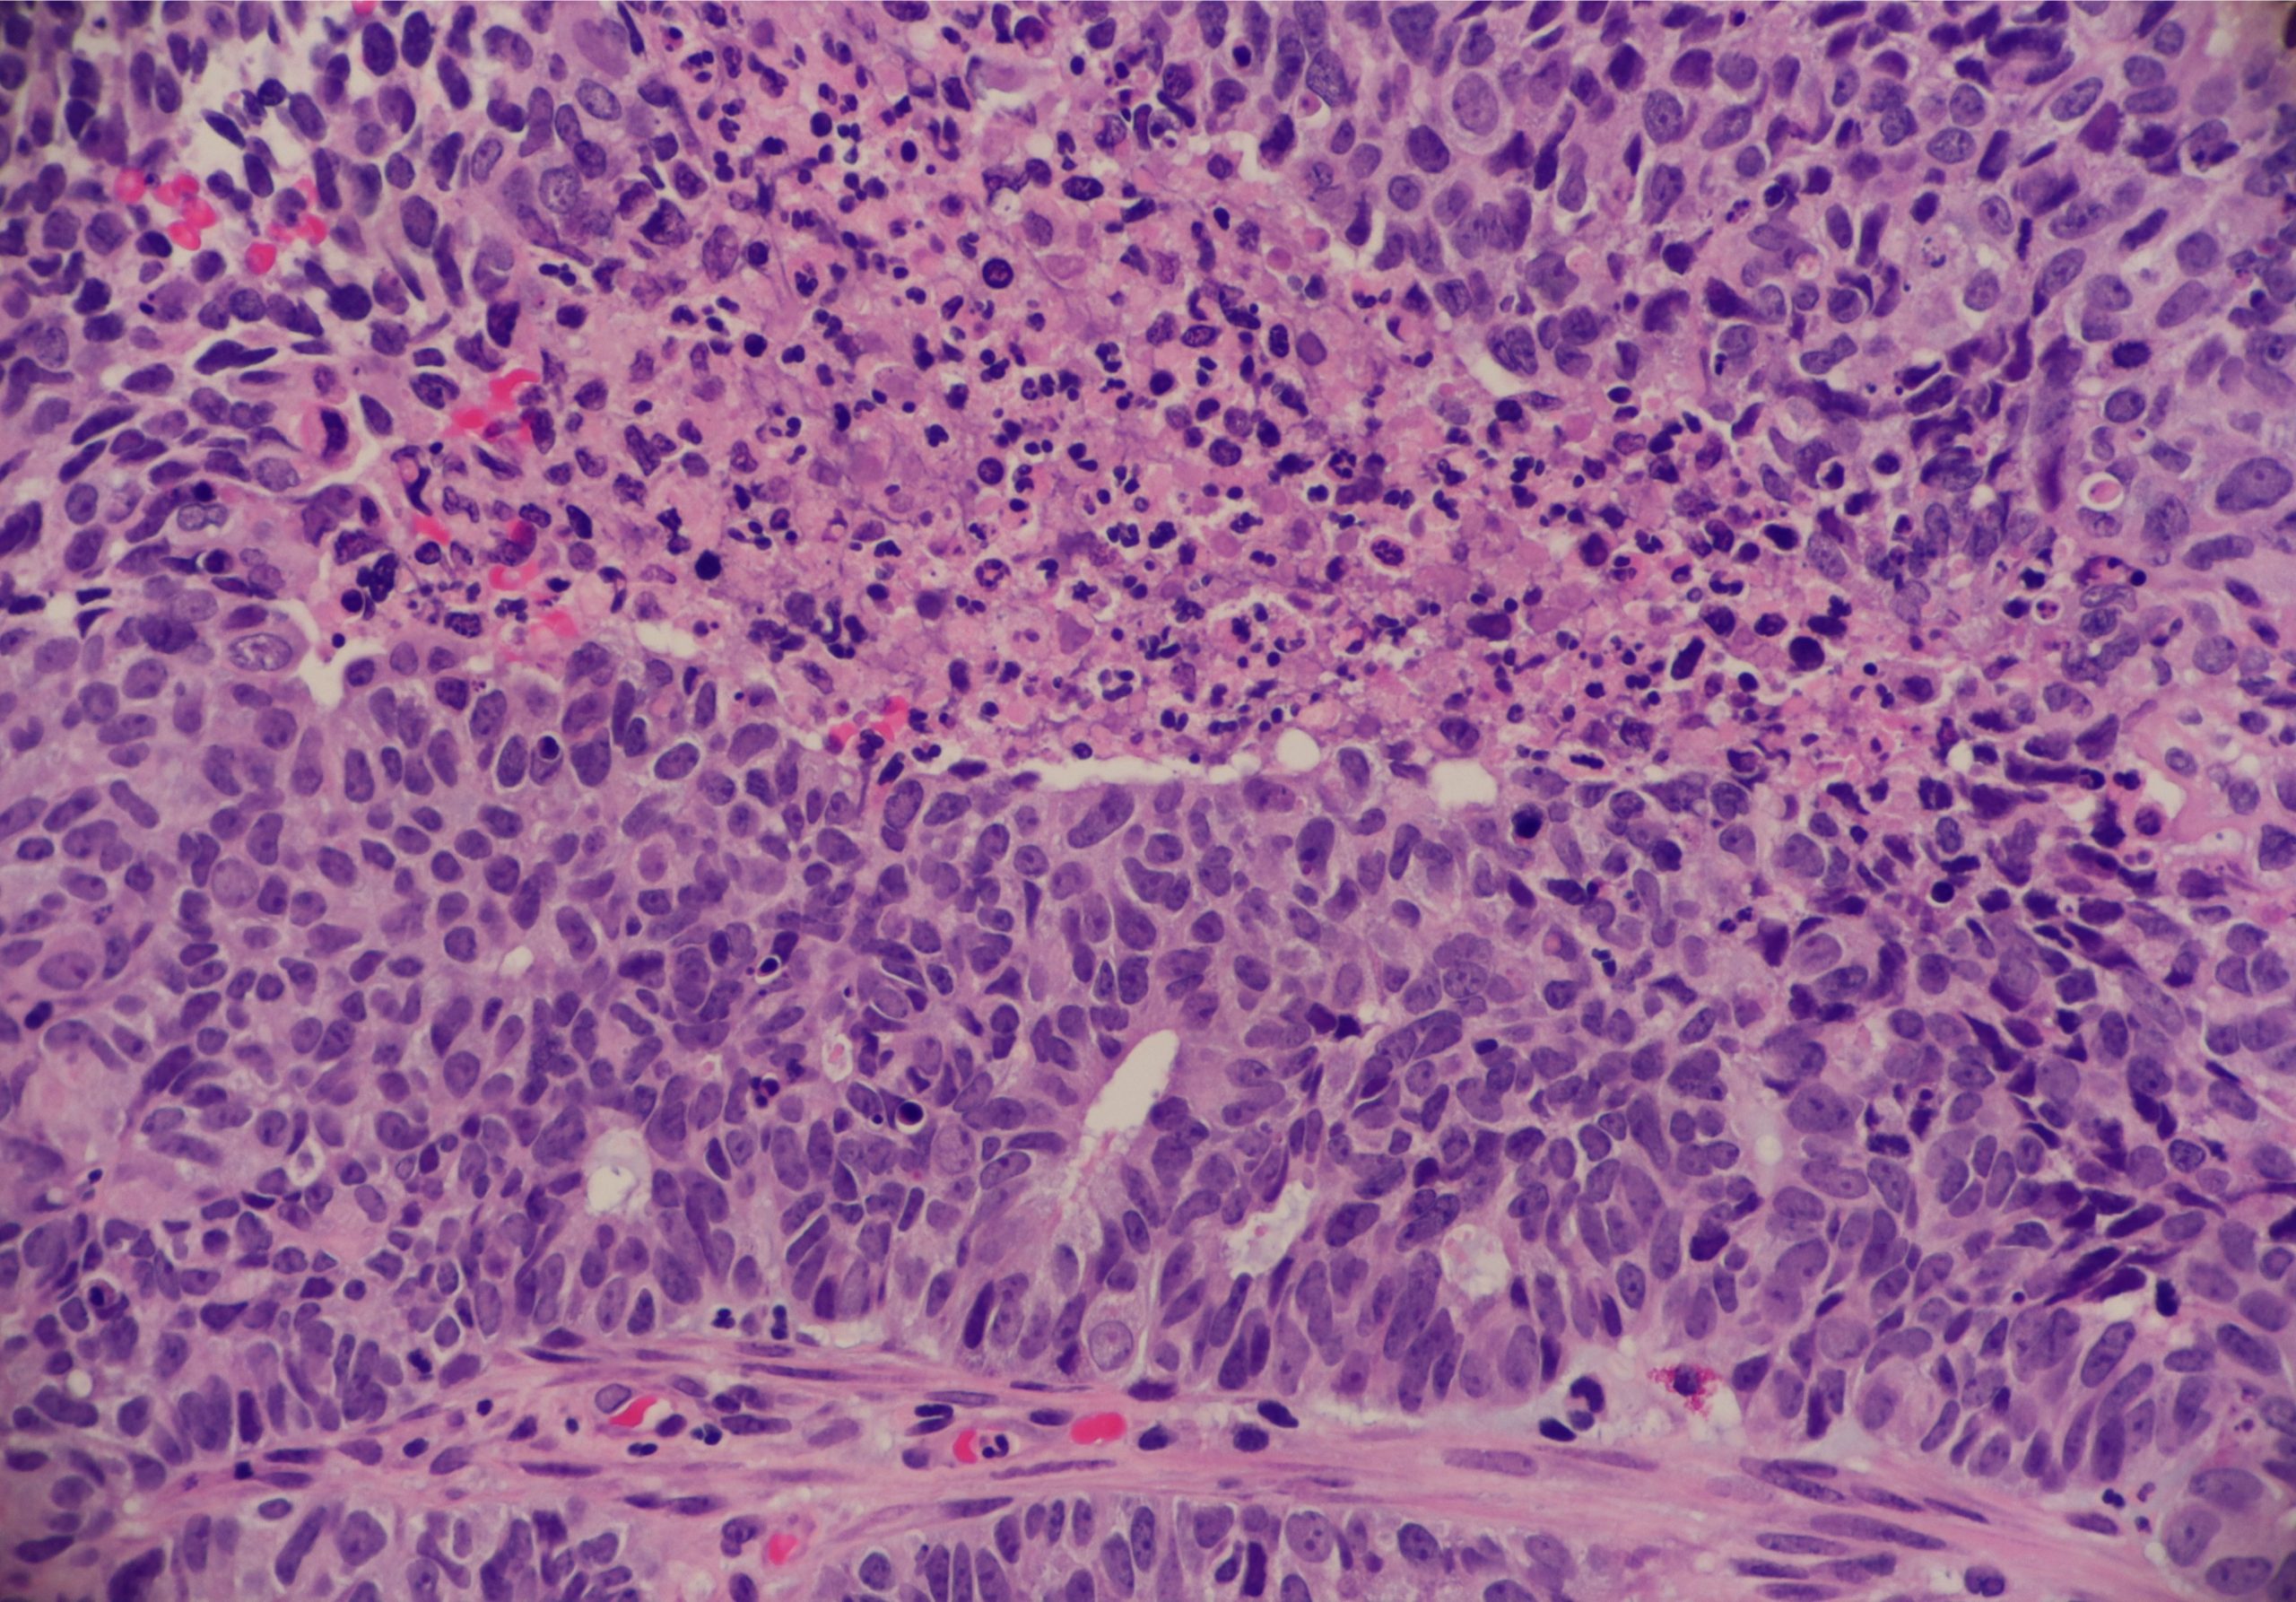

凝固壊死

凝固壊死の特徴は、死んだ組織が固形化することです。

組織内のタンパクが変性し、ゲル・固形化するために

壊死の様子が構造物として確認可能。

凝固壊死は多くの悪性腫瘍でみられる様式で、

心臓をはじめとする臓器の梗塞によっても生じます

乾酪壊死

乾酪壊死は凝固壊死と融解壊死の特徴を併せ持ち

結核や真菌の感染、その他外的要因によって生じます

肉眼的にカッテージチーズのような見た目であるため、

乾酪壊死と呼ばれます。